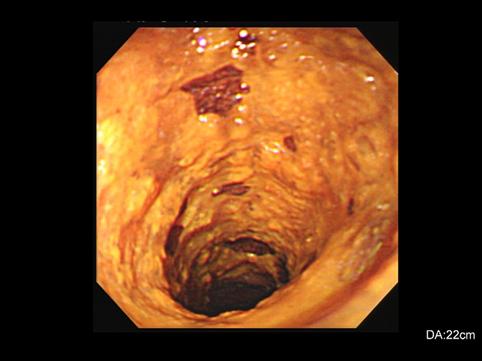

疾患(病理主体)の分類悪性上皮性腫瘍/扁平上皮癌

部位(臓器別)食道/中

検査方法内視鏡

腫瘍の肉眼分類0型(表在型)/IIc型(IIc)

病変の最大径(ミリ)40以上

腫瘍の深達度m